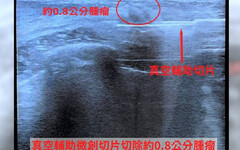

2025-11-12 00:09:00 | 大成報【警政時報 張家燁/新竹報導】24歲年輕女子因乳房疼痛求診中國醫…

2025-11-10 21:00:00 | 健康醫療網24歲年輕女性乳房疼痛,原來是腫瘤作祟。(圖/中國醫藥大學新竹附…